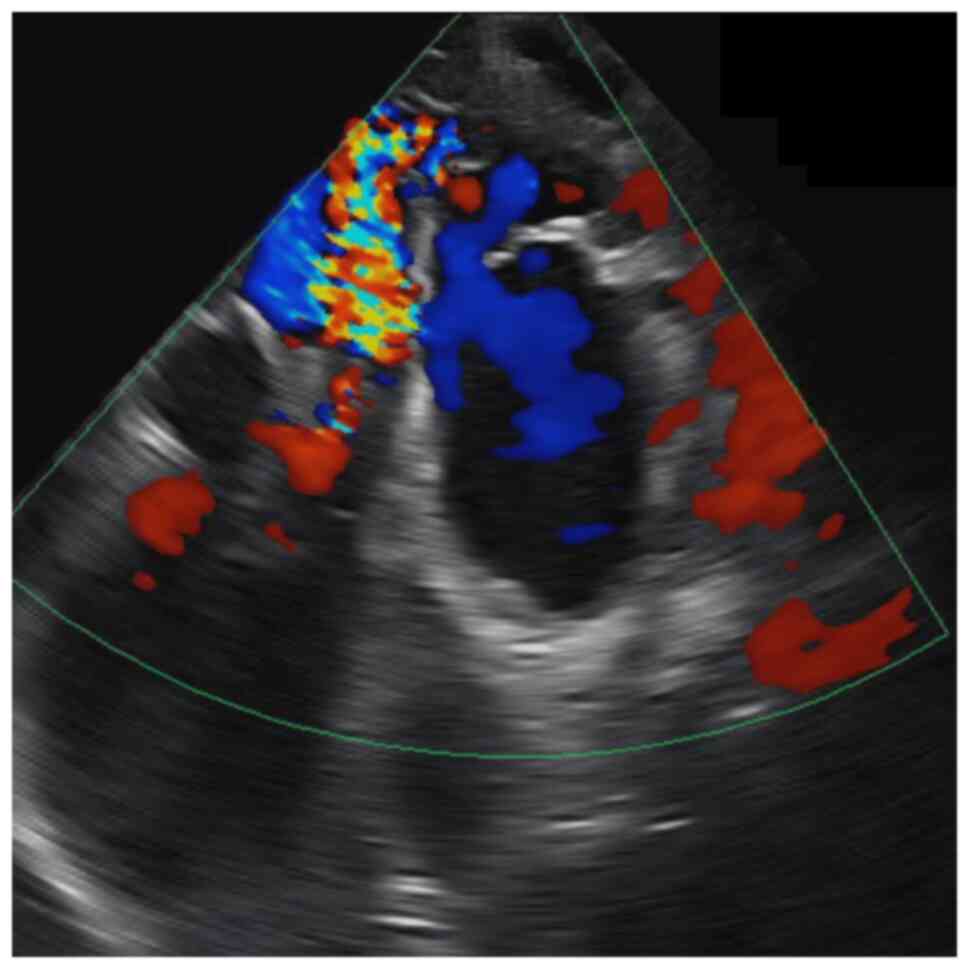

Intracranial vein of Galen malformation and its management: A case report

Vein of Galen malformation (VOGM) is a rare congenital arteriovenous malformation affecting the pediatric population, characterized by a fistula between the diencephalon and a dilated vein of Galen. The present study reports the case of a 6‑month‑old male infant referred for developmental delays and abnormal head circumference. A clinical examination revealed macrocephaly, dilated scalp veins and neurological abnormalities. Neuroimaging confirmed a large VOGM with associated hydrocephalus. A multidisciplinary team devised a treatment plan involving endovascular embolization and ventriculoperitoneal shunt placement. The post‑operative recovery exhibited an improvement in neurodevelopmental milestones and a reduced head circumference. Generally, the management of VOGM requires a comprehensive approach, including early diagnosis, precise imaging and timely intervention. The case described herein highlights the importance of interventional radiology in planning a management plan and the novel kissing microcatheter endovascular embolization technique.

Figure 1